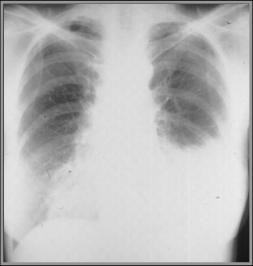

Anaerobic pneumonia with effusion